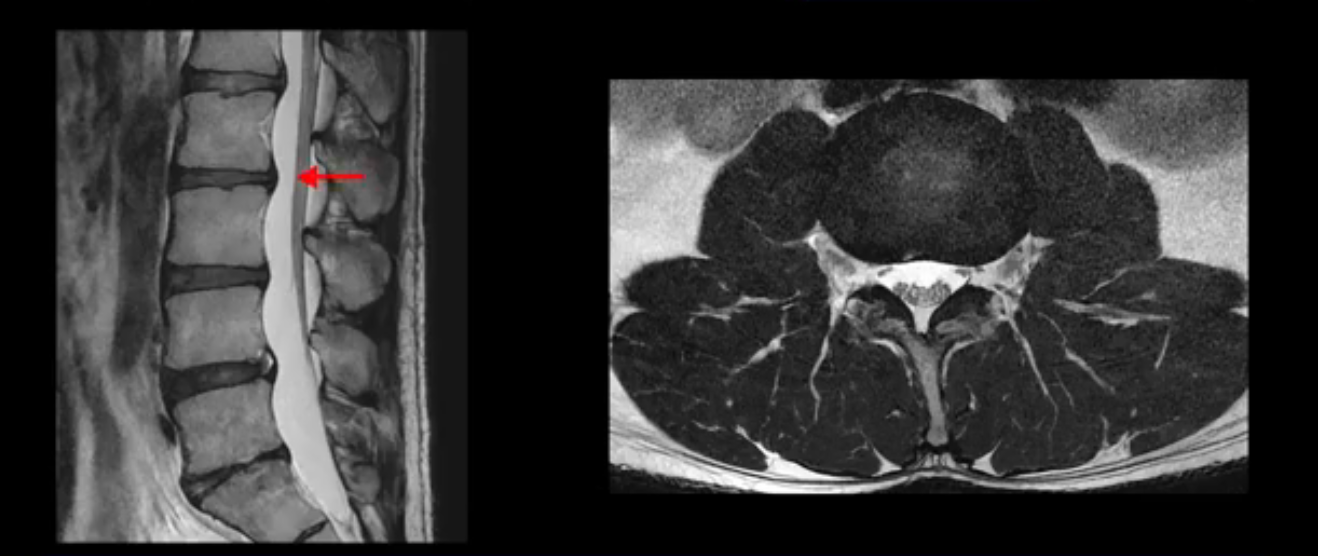

그런데 이분의 증상과 MRI가 전혀 일치하지 않는데, 왜 그런지 지금부터 자세히 설명드립니다. 이분 증상은 앉으면 엉치와 허리가 심하게 아파 10분 이상 앉는 게 어렵고 양쪽 발가락이 앉아있을 때나 누워있을 때 다 저립니다. 걸을 때도 아파서 10분 걷기도 어렵습니다. MRI를 마디마디 살펴보면 1번 2번은 오른쪽으로 살짝 밀려나온 디스크가 있지만 전혀 심하지 않고, 뒤에 또 설명하겠지만 최근에 밀려나온 급성 디스크가 아니고 오래된 디스크로 판단됩니다.

2번 3번도 비교적 디스크 상태는 좋고 신경 구멍 넓이도 아주 넓습니다.

추간공도 보시다시피 왼쪽, 오른쪽 전부 다 매우 넓어서 신경이 눌릴만한 부분이 전혀 보이지 않습니다.